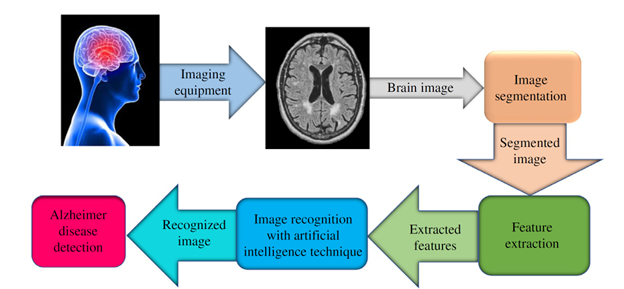

While fundamental research lays the groundwork, the ultimate goal is to translate insights into tools that improve patient care. In this realm, AI has become indispensable.

- Alzheimer’s Disease Detection

Deep learning frameworks can analyze T2-weighted MRI scans to differentiate healthy aging from Alzheimer’s pathology with accuracies nearing 98%. This empowers clinicians with objective, reproducible diagnostic support.

Figure 2 Machine learning pipeline for MRI-based Alzheimer’s diagnosis.